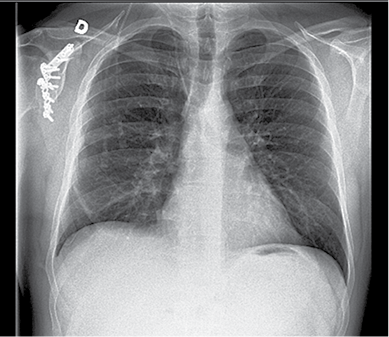

36 m. vyras P. D. atvyko į Gastroenterologijos skyrių patikslinti diagnozės planine kepenų biopsija. Praėjus 8 val. po procedūros, pacientas pajuto maudimą po dešiniuoju šonkaulių lanku punkcijos vietoje. Apžiūros metu pacientas buvo hemodinamiškai stabilus. Atlikus laboratorinius tyrimus, nustatyta saiki anemizacija (hemoglobinas – 128 g/l; norma – 135–160 g/l). Įtariant kraujavimą pilvaplėvėje, atlikta pilvo echoskopija: pilvo ertmėje laisvo skysčio nematyti, dešinėje pleuroje iki 4 cm laisvo skysčio ruožas. Konsultuota krūtinės chirurgo. Rekomenduota atlikti krūtinės ląstos rentgenogramą (Ro). Nustatytas beveik neoringas dešinysis plautis, pastebėta hidrotorakso požymių (1 pav.). Įtarus jatrogeninį hemotoraksą, krūtinės chirurgas atliko diagnostinę pleuros punkciją. Patvirtinus hemotorakso diagnozę, drenuota dešinė pleuros ertmė, išsiskyrė 400 ml kraujo. Tuo metu aktyvaus kraujavimo nenustatyta, hemodinamika išliko stabili, kartotiniuose laboratoriniuose tyrimuose – saiki anemizacija (hemoglobinas – 120 g/l). Atlikus kontrolinę rentgenogramą, nustatytas sumažėjęs skysčio kiekis pleuroje, buvo matyti kompresinių dešiniojo plaučio pakitimų. Įtariant sukrešėjusį hemotoraksą, atlikta skubi krūtinės ląstos KT (2 pav.), kuri patvirtino įtariamą patologiją. Tolesniam operaciniam gydymui pacientas perkeltas į Krūtinės chirurgijos skyrių. Atlikta skubi VATS (angl. video assisted thoracoscopic surgery). Operacijos metu pašalinta 1 000 ml krešulių, aktyvaus kraujavimo nenustatyta, diafragmos kupole rasta nedidelė hematoma. Pooperacinis periodas sklandus (3 pav.). Po trijų dienų geros būklės pacientas išleistas į namus.

1 pav. Krūtinės ląstos priekinė rentgenograma prieš operaciją